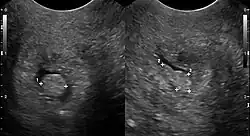

Polypen sind makroskopisch sichtbare, meist gestielte Ausstülpungen der Mukosa (Schleimhaut).

Häufig treten Polypen als Adenome im Darm auf. Dort können sie im Rahmen einer Darmspiegelung mittels der Polypektomie entfernt werden, da die Gefahr einer Entwicklung zum Darmkrebs besteht (Adenom-Karzinom-Sequenz).